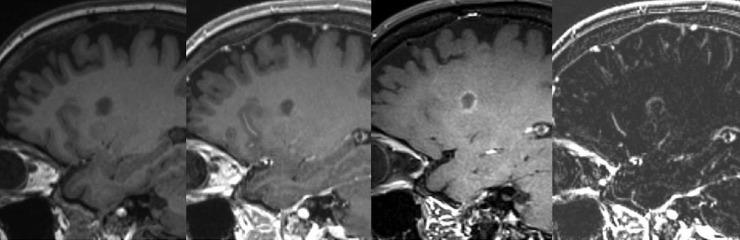

In multiple sclerosis (MS) the sensitivity for detection of contrast enhancing lesions (CEL) in T1-weighted scans is essential for diagnostics and therapy decisions. The purpose of our study was to evaluate the sensitivity of T1w MPRAGE scans in comparison to T1w dark blood technique (T1-DB) for CEL in MS.

MATERIALS AND METHODS

3T MR imaging was performed in 37 MS patients, including T2-weighted imaging, T1w MPRAGE before and after gadolinium injection (unenhanced-T1 and T1-CE) and T1-DB imaging. After gadolinium application, the T1-DB scan was performed prior to T1-CE. From unenhanced-T1 and T1-CE scans, subtraction images (T1-SUB) were calculated. The number of CEL was determined separately on T1-CE and T1-DB by two raters independently. Lesions only detected on T1-DB scans then were verified on T1-SUB. Only lesions detected by both raters were included in further analysis.

RESULTS

In 16 patients, at least one CEL was detected by both rater, either on T1-CE or T1-DB. All lesions that were detected on T1-CE were also detected on T1-DB images. The total number of contrast enhancing lesions detected on T1-DB images (n = 54) by both raters was significantly higher than the corresponding number of lesions identified on T1-CE (n = 27) (p = 0.01); all of these lesions could be verified on SUB images. In 21 patients, no CEL was detected in any of the sequences.

CONCLUSIONS

The application of T1-DB technique increases the sensitivity for CEL in MS, especially for those lesions that show only subtle increase in intensity after Gadolinium application but remain hypo- or iso-intense to surrounding tissue.

在多发性硬化症(MS)中,T1加权扫描中检测对比增强病灶(CEL)的敏感性对于诊断和治疗决策至关重要。我们研究的目的是评估T1加权MPRAGE扫描与T1加权黑血技术(T1-DB)相比对MS中CEL的敏感性。

材料与方法

对37例MS患者进行3T磁共振成像,包括T2加权成像、钆注射前后的T1加权MPRAGE(未增强T1和T1-CE)以及T1-DB成像。应用钆后,在T1-CE之前进行T1-DB扫描。从未增强T1和T1-CE扫描中计算减法图像(T1-SUB)。两名评估者分别在T1-CE和T1-DB上确定CEL的数量。然后在T1-SUB上验证仅在T1-DB扫描中检测到的病灶。仅两名评估者均检测到的病灶纳入进一步分析。

结果

在16例患者中,两名评估者在T1-CE或T1-DB上均检测到至少一个CEL。在T1-CE上检测到的所有病灶在T1-DB图像上也被检测到。两名评估者在T1-DB图像上检测到的对比增强病灶总数(n = 54)显著高于在T1-CE上识别的相应病灶数(n = 27)(p = 0.01);所有这些病灶均可在SUB图像上得到验证。在21例患者中,任何序列均未检测到CEL。

结论

T1-DB技术的应用提高了MS中CEL的敏感性,特别是对于那些在应用钆后强度仅轻微增加但对周围组织仍呈低或等强度的病灶。